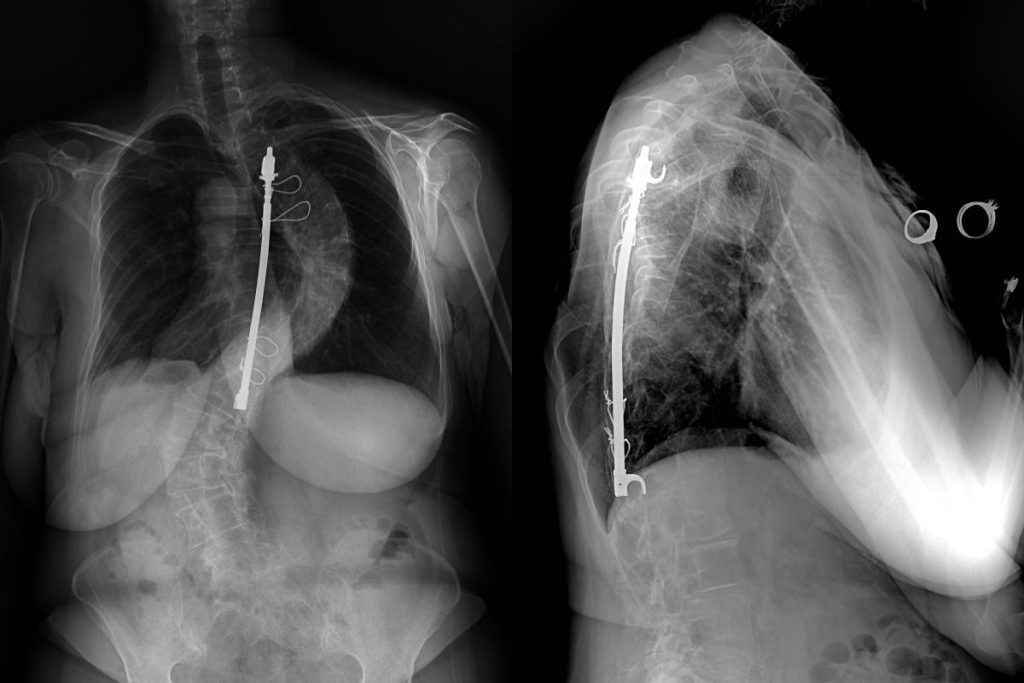

From www.sciencephoto.com

Harrington rod spinal implants in scoliosis, Xray Stock Image C052 Harrington Rod Material Since the introduction of the harrington rod in 1962, new rod materials and concepts have been developed. Rigid rod fixation has achieved higher fusion rates than. The straight rod, containing a ratcheting mechanism, is positioned along the inside or. It's attached to the spine with the goal of holding it in a straighter position so its vertebrae can't become more.. Harrington Rod Material.